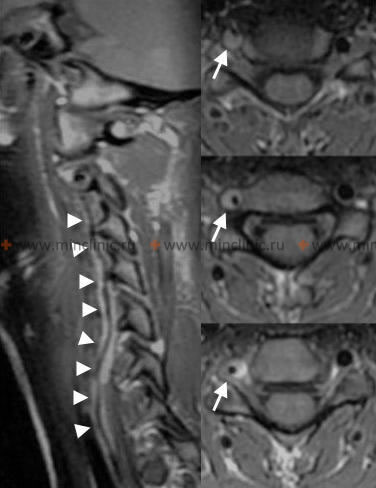

- თავის ტვინის მრტ: არჩევის ვიზუალიზაციის მეთოდი. დიფუზია-შეწონილი ვიზუალიზაციის (DWI) რეჟიმები ძალიან მგრძნობიარეა მწვავე იშემიის გამოსავლენად წუთებიდან საათებში, ნათლად აჩვენებს ინფარქტებს მოგრძო ტვინსა და ნათხემში. FLAIR რეჟიმები ეხმარება ინფარქტის ხანდაზმულობის შეფასებაში, ხოლო GRE/SWI რეჟიმებს შეუძლიათ გამოავლინონ მცირე სისხლჩაქცევები ან დისექციის ნიშნები.

- სისხლძარღვოვანი ვიზუალიზაცია: გადამწყვეტია ძირითადი მიზეზის დასადგენად (ოკლუზია, სტენოზი, დისექცია) [4, 5].

- თავისა და კისრის კტა (კომპიუტერულ-ტომოგრაფიული ანგიოგრაფია): სწრაფად მიიღება, უზრუნველყოფს VA და პროქსიმალური PICA-ს კარგ ვიზუალიზაციას, გამოსადეგია მნიშვნელოვანი სტენოზის, ოკლუზიის ან დისექციის ნიშნების გამოსავლენად.

- თავისა და კისრის მრა (მაგნიტურ-რეზონანსული ანგიოგრაფია): არაინვაზიური ალტერნატივა, კარგია სკრინინგისთვის, მაგრამ შეიძლება ნაკლებად ზუსტი იყოს, ვიდრე კტა/დსა სტენოზის ხარისხის ან მცირე დისექციის შესაფასებლად. მაღალი ველის მრა (მაგ., 3 ტესლა) გვთავაზობს გაუმჯობესებულ რეზოლუციას.